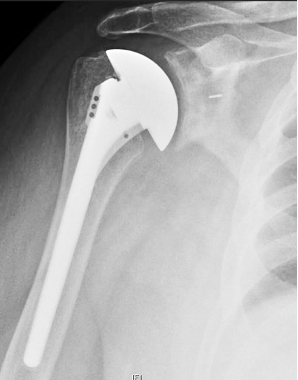

Dr Frederick Matsen

@shoulderarth

A Professor in the Department of Orthopaedics at the University of Washington; a shoulder reconstructive surgery and shoulder arthritis specialist.